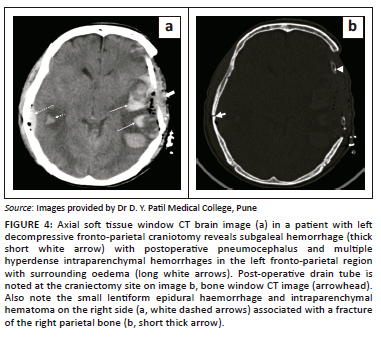

Post-operative haemorrhages

Small scalp and extradural haemorrhages are relatively common and benign findings in the post-operative period. Only about 1% of post-craniotomy intracranial haemorrhages require surgical intervention.8 The most common post-operative haematomas are intraparenchymal (43%) (Figure 4), extradural haematoma (33%), subdural haematoma (5%) and mixed (8%) (Figure 5).8

Extradural haematomas are situated between the dura and the inner table of the skull. The majority of the post-operative extradural hematomas are regional, in the location related to the surgical site.9 Further subtypes are adjacent haematomas that occur at the margins of the craniotomy site and remote extradural haematomas, located distant from the craniotomy site.10 The majority of intraparenchymal haemorrhages are small (less than 3 cm in size) and do not cause much neurological compromise. Large haematomas are associated with poorer outcomes.1 Causes of large intraparenchymal haemorrhages include poor haemostasis, excessive brain retraction, hypertension in the post-operative period and bleeding disorders.